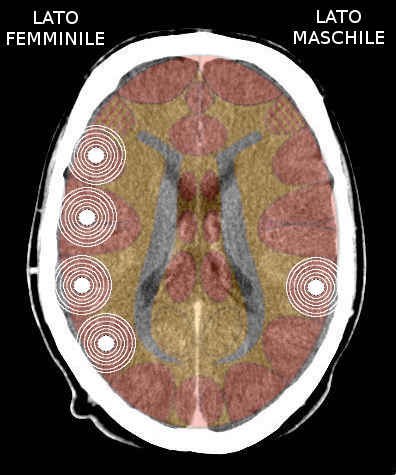

- Requisiti: Si è in costellazione schizofrenica quando due attivazioni colpiscono i due emisferi cerebrali di uno stesso livello:

- le due emiparti del tronco cerebrale;

- i due emisferi cerebellari;

- i due emisferi cerebrali (midollo e/o corteccia).

- NON È COSTELLAZIONE quando due attivazioni interessano due livelli cerebrali differenti, anche se occupano i due emisferi.

Possono esserci due o più costellazioni schizofreniche anche su livelli differenti (ad es. una costellazione corticale e una cerebellare) - I relè cerebrali: In una costellazione si possono avere: